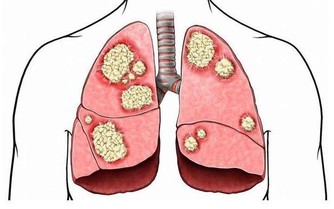

肝臟是人體內最大的腺體,主要功能是儲藏、代謝和解毒以及分泌膽汁。

當人們高強度勞動後,肝會進行各種代謝,以補充體內消耗的能源。

對肝威脅最大的是肝炎、肝硬化和肝癌。經常過量飲酒的人群,肝硬化和肝癌的機會比一般人高得多。